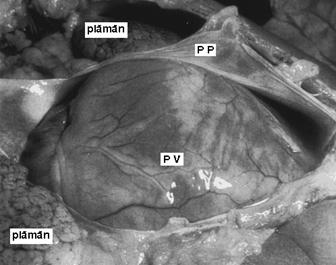

Pericardul este un sac fibroelastic seros inchis care se afla posterior fata de stern in dreptul coastelor II-VI si anterior fata de vertebrele V-VIII. In cursul dezvoltarii embrionare, cordul invagineaza acest sac pana la nivelul pediculului vaselor mari (aorta, vene cave si artera pulmonara). Stratul de contact intim cu miocardul este pericardul visceral sau epicardul (seroasa subtire, fara strat fibros) si acopera intreg cordul in afara unei arii posterioare a AS dintre venele pulmonare numita sinus oblic; zona dintre vasele mari in care epicardul se reflecta asupra sa insasi pentru a forma pericardul parietal se numeste sinus transvers.

Pericardul parietal are conventional doua straturi intim

aderente, unul extern si unul intern; cel extern este compus din multiple

straturi de fibre de colagen aliniate in diverse directii si

interconectate cu fibre de elastina. Stratul fibros fixeaza cordul

prin ligamente atasate de tendonul central al diafragmului (inferior), de stern prin ligamente sterno-pericardice

anterioare si inferioare si de pleura (lateral). Stratul intern

al pericardului parietal este o membana mezoteliala seroasa cu

microvili care secreta lichidul pericardic hipoproteic cu multa

albumina (ultrafiltrat plasmatic) aflat fiziologic intr-o cantitate de

15-50 ml.